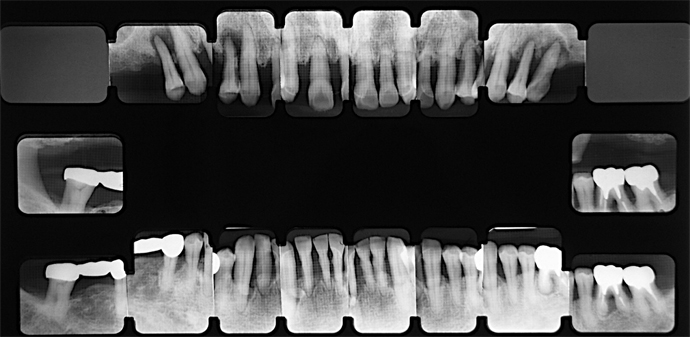

初診

上顎臼歯部は欠損で前歯部は歯周病が進行し歯の位置にも変化が見られました。また下顎も全体的に歯周病が進行し、このままでは早々に歯が抜けて大きな義歯の装着を余儀なくされる状態でした。

治療計画

初診時のレントゲンです。上下顎とも歯周病が進行しており、根の先まで骨が吸収している歯もあります。

治療内容は抜歯、再生療法を含む歯周治療、インプラント治療、義歯の総合治療で、とくに治療が進むにつれ、自身の歯に対する可能な限り保存してほしいとの希望が強く感じられました。下顎はインプラントを含み固定式で、上顎は前歯を保存しながらオーバーデンチャーという大きな義歯で対応する予定でしたが、前歯部はブリッジで、奥歯は義歯で対応し、義歯を外しても歯がある形を治療目標としました。